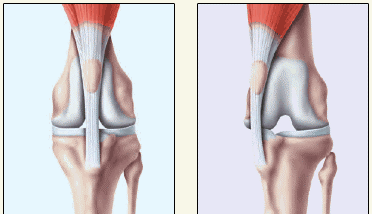

Neben der Versorgung von Knochenbrüchen führen wir auch Gelenksoperationen, wie hier die Korrektur einer

Verlagerung der Kniescheibe (Patellaluxation) nach innen, wie sie häufig bei Kleinhundrassen vorkommt, durch. Das Kniegelenk wurde eröffnet, der Ansatz des geraden Kniescheibenbandes mit der Tuberositas tibiae abgesägt, der Ansatz nach außen versetzt und mit einem Bohrdraht befestigt. Nach der Operation steht das Knie und die Kniescheibe wieder korrekt

Die Kniescheibe ist bei kleine Hunden häufig nach innen verlagert

Das sieht dann so aus, sie liegt neben dem Gelenk